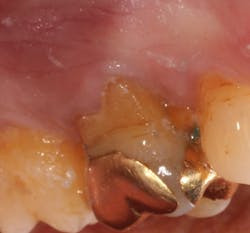

A 69-year-old male with a noncontributory medical history presented with 5 mm of recession, less than 1 mm of attached gingiva, and cervical notching on tooth No. 3. The tooth had an existing gold onlay and was caries-free (figures 1a and 1b). Radiographic analysis showed periodontal bone loss and a radiolucency at the apex of the tooth. The patient denied implant therapy and wanted to save the tooth.